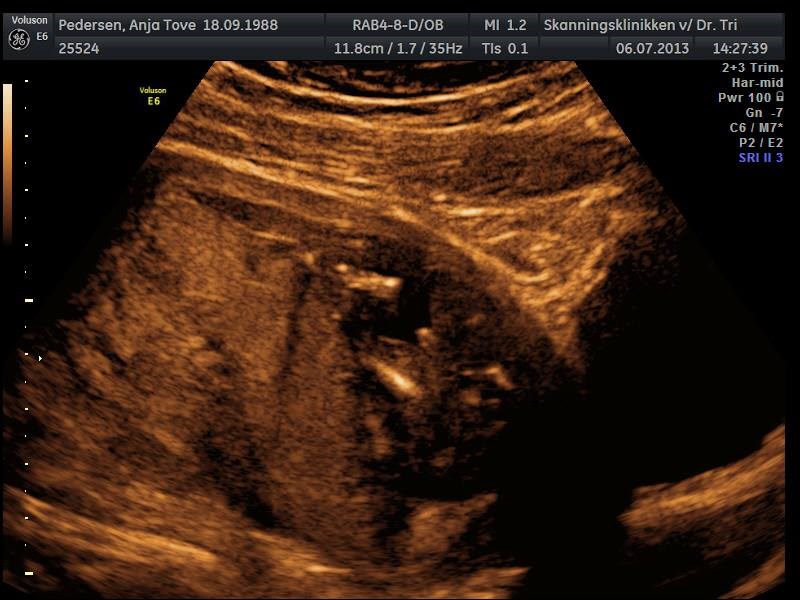

Helt igennem perfekt DRENG

Han er lige præcis som han skal være, dog ikke en særlig fotogen dreng  Han gemte sig hver gang vi troede der var et godt billed, men det betyder bare at vi har fået en masse billeder og en masse filmklip af ham

Da hun skulle se kønnet fik hun lige skyggen af en tissemand, men hurtigt fik lilledrengen en hånd ned på den, for den skulle vi i hvert fald ikke se  Men efter lidt tid viste han dog den stolt frem alligevel

Ud over det så vi ham sutte på tommelfinger og på hans storetå og vi så ham have hikke  Og så var der bare så meget bevægelse i ham, fantastisk at se  Vi fik også et glimt af ham i 3d, men han ville ikke være med til det så vi så kun lidt bevægelse og et halvt ansigt

Nå, men nu kan i da lige få et billede hvor der i hvert fald ikke er tvivl